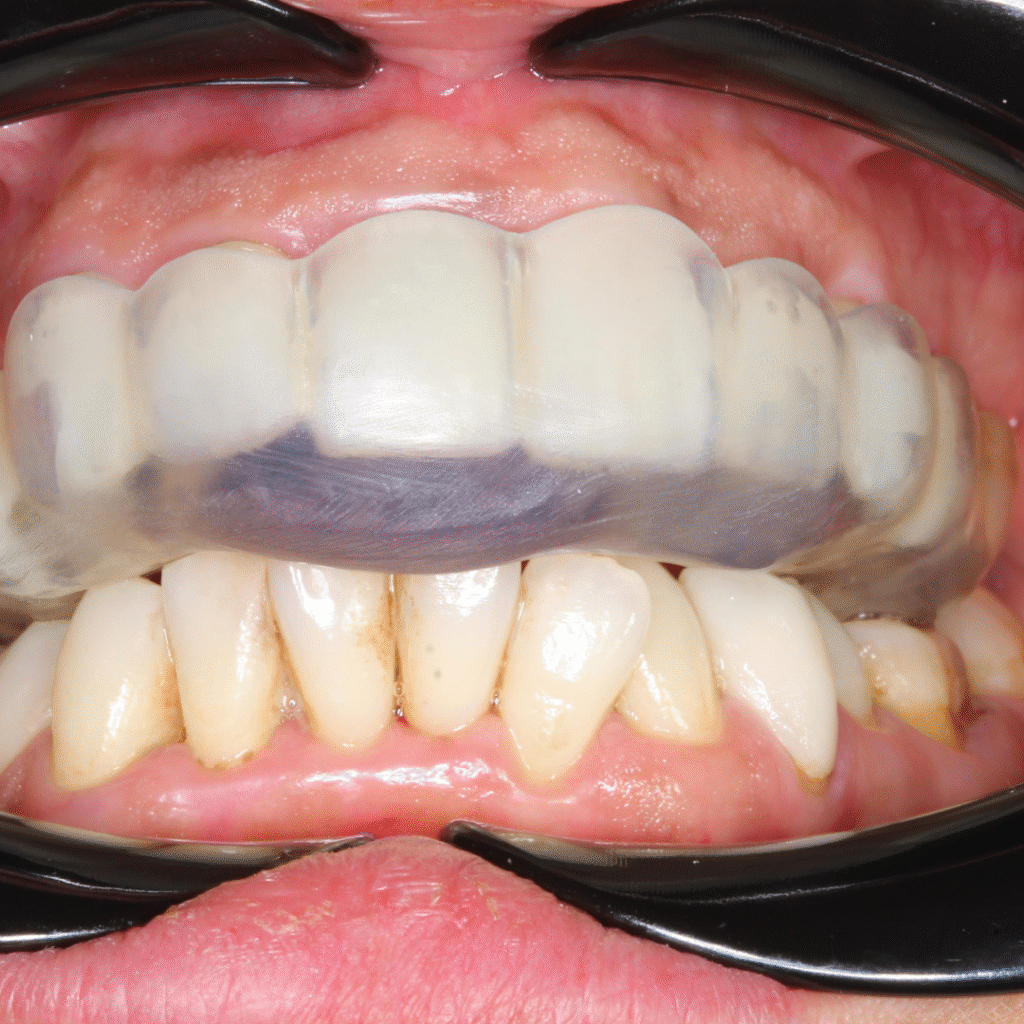

TMJ Splint Treatment

drosmanakinciTMJ Splint Treatment in Türkiye: Get the most affordable TMJ splint in 1 day! Temporomandibular…

TMJ Orthotic Treatment

drosmanakinciTMJ Orthotic Treatment in Turkey: Relieve Pain and Restore Harmony Temporomandibular Joint (TMJ) disorders can…